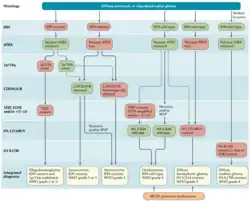

Glioblastoma classification

Brain tumor classification has been traditionally based on histopathology at macroscopic level, measured in hematoxylin-eosin sections. The World Health Organization published the first standard classification in 1979[34] and has been doing so since. The 2007 WHO Classification of Tumors of the Central Nervous System[35] was the last classification mainly based on microscopy features. The new 2016 WHO Classification of Tumors of the Central Nervous System[36] was a paradigm shift: some of the tumors were defined also by their genetic composition as well as their cell morphology.

In 2021, the fifth edition of the WHO Classification of Tumors of the Central Nervous System was released. This update eliminated the classification of secondary glioblastoma and reclassified those tumors as Astrocytoma, IDH mutant, grade 4. Only tumors that are IDH wild type are now classified as glioblastoma.[37]

There are currently three molecular subtypes of glioblastoma that were identified based on gene expression:[39]

- Classical: Around 97% of tumors in this subtype carry extra copies of the epidermal growth factor receptor (EGFR) gene, and most have higher than normal expression of EGFR, whereas the gene TP53 (p53), which is often mutated in glioblastoma, is rarely mutated in this subtype.[40] Loss of heterozygosity in chromosome 10 is also frequently seen in the classical subtype alongside chromosome 7 amplification.[41]

- The proneural subtype often has high rates of alterations in TP53 (p53), and in PDGFRA the gene encoding a-type platelet-derived growth factor receptor.[42]

- The mesenchymal subtype is characterized by high rates of mutations or other alterations in NF1, the gene encoding neurofibromin 1 and fewer alterations in the EGFR gene and less expression of EGFR than other types.[43]

Initial analyses of gene expression had revealed a fourth neural subtype.[42] However, further analyses revealed that this subtype is non-tumor specific and is potential contamination caused by the normal cells.[39]

Many other genetic alterations have been described in glioblastoma, and the majority of them are clustered in two pathways, the RB and the PI3K/AKT.[44] 68–78% and 88% of Glioblastomas have alterations in these pathways, respectively.[6]

Distinguishing glioblastoma from high-grade astrocytoma is important. These tumors occur spontaneously (de novo) and have not progressed from a lower-grade glioma, as in high-grade astrocytomas.[6] Glioblastomas have a worse prognosis and different tumor biology, and may have a different response to therapy, which makes this a critical evaluation to determine patient prognosis and therapy.[45][62] Astrocytomas carry a mutation in IDH1 or IDH2, whereas this mutation is not present in glioblastoma. Thus, IDH1 and IDH2 mutations are a useful tool to distinguish glioblastomas from astrocytomas, since histopathologically they are similar and the distinction without molecular biomarkers is unreliable.[46] IDH-wildtype glioblastomas usually have lower OLIG2 expression compared with IDH-mutant lower grade astrocytomas.[63] In patients aged over 55 years with a histologically typical glioblastoma, without a pre-existing lower grade glioma, with a non-midline tumor location and with retained nuclear ATRX expression, immunohistochemical negativity for IDH1 R132H suffices for the classification as IDH-wild-type glioblastoma.[60] In all other instances of diffuse gliomas, a lack of IDH1 R132H immunopositivity should be followed by IDH1 and IDH2 DNA sequencing to detect or exclude the presence of non-canonical mutations.[60] IDH-wild-type diffuse astrocytic gliomas without microvascular proliferation or necrosis should be tested for EGFR amplification, TERT promoter mutation and a +7/–10 cytogenetic signature as molecular characteristics of IDH-wild-type glioblastomas.[60]